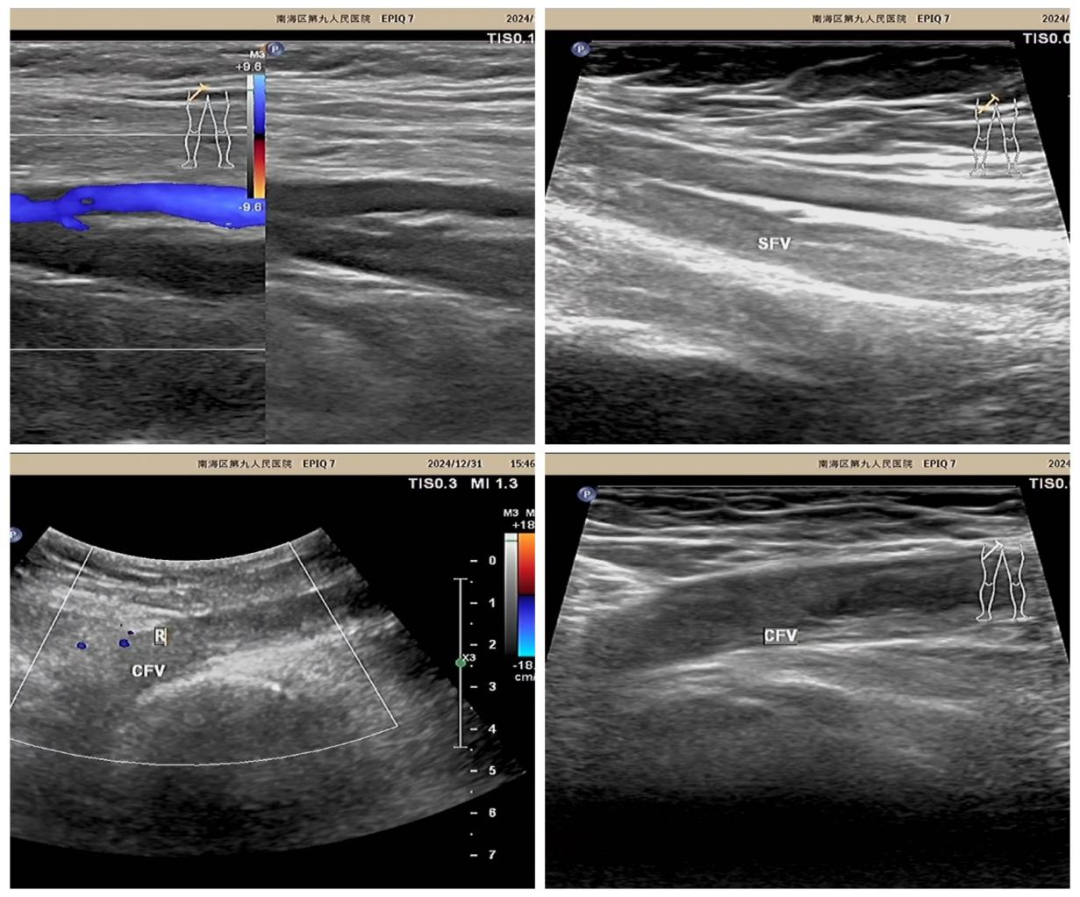

前段时间,李女士因右侧股骨颈骨折术后来到南海九院功能科进行右下肢血管彩超检查,彩超检查发现患者右侧股总静脉及股浅静脉存在血栓。检查期间李女士突然说:“医生,我呼吸很辛苦,后背也痛”

(超声检查:右侧股总静脉、股静脉血栓)